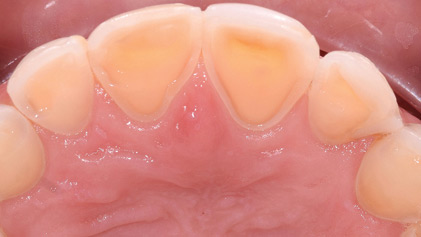

An Overview on Dental Wear

Rotella-thumbnail alternate text for this image

Dental wear is a general term that can be used to describe the surface loss of dental hard tissues from causes other than dental caries, trauma or as a result of developmental disorders. It is a normal physiological process that is macroscopically irreversible; Lambrechts et al.1 estimated the normal vertical loss of enamel from physiological … Read more